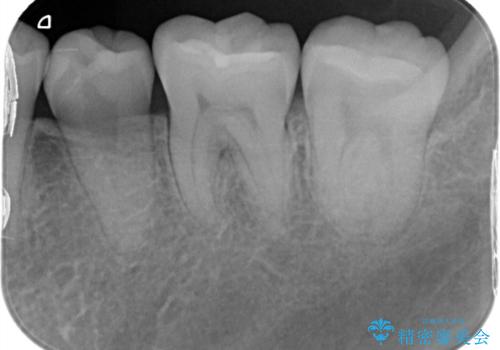

- 昔保険で治療した詰め物の形をずっと気にされていた患者様です。また下の歯なのでお口を開けると見えてしまうことを気にされていました。白く丈夫な被せ物を奥歯に入れたいと希望されたため、セラミックインレーにて治療いたしました。

保険でよく使用されるコンポジットレジンが詰めてありました。時間が経つと劣化しやすい材質なため全て取り除き、形を整えてセラミックインレーを被せました。キレイな歯の形を手に入れることができ、ご満足いただけました。